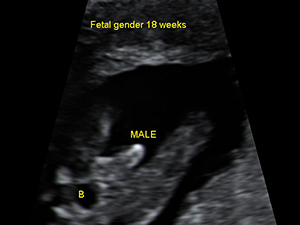

The fetal hand at 20 weeks Gender - Male

Male genital organ (arrow) at 18 weeks

Male genital organ (arrow) at 18 weeks Gender - Female